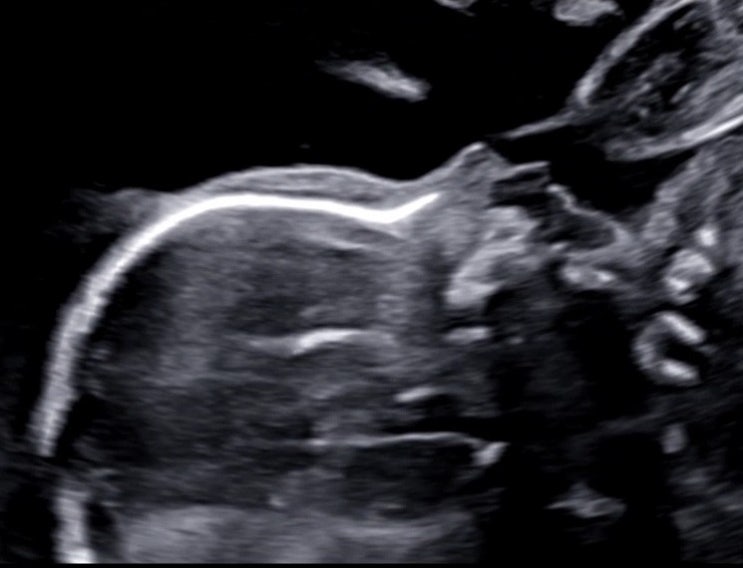

30-33주차, 입체초음파 재도전 성공!!

28주차에 시도했던 입체초음파 뿌용이 얼굴보기는 대차게 실패했다. '태어나면 얼굴보지 뭐' 라...

28주차, 입체초음파로 얼굴보기 실패!

28주차 입체초음파로 뿌용이의 얼굴을 확인하는 날. 워낙 태동이 활발한 아기어서 전혀 걱정하지 않았건만 ...